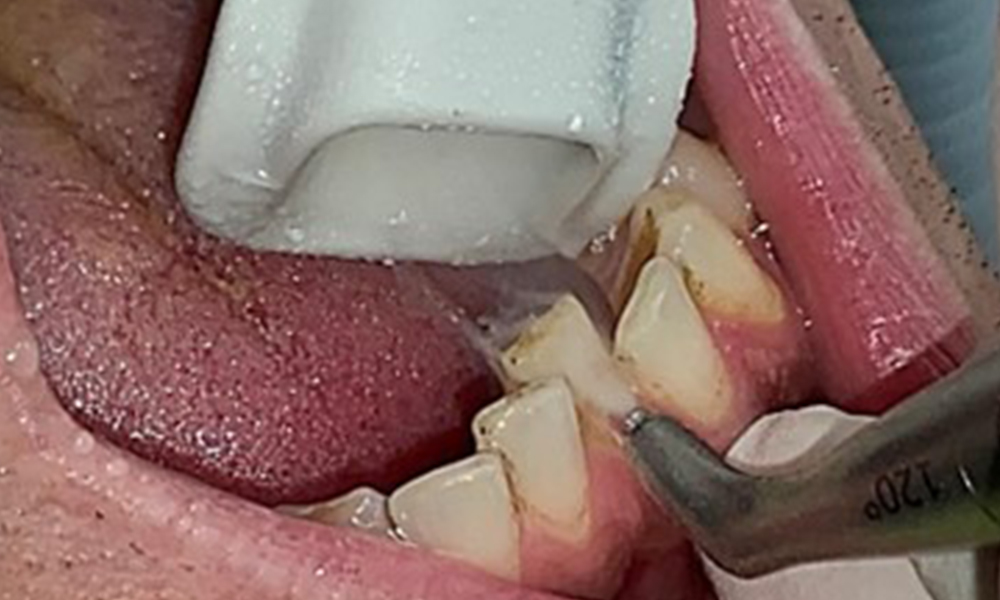

Due to the otherwise favourable general medical condition, the needs determined during the intraoral examination will be decisive for their treatment. It will be essential to periodically determine the probing depths. Gingival bleeding decreases in smokers, which is why the clinical diagnosis of periodontitis can only be made by probing (Fig. 7). Placing exclusive focus on the determination of bleeding indices may obscure existing periodontitis or gingivitis. (5)

The objective would be to control disease risk by removing supragingival and subgingival biofilm. The instruments can be selected based on patient needs. First, calculus and any concretions must be removed using ultrasonic and/or manual instruments (Fig. 10).